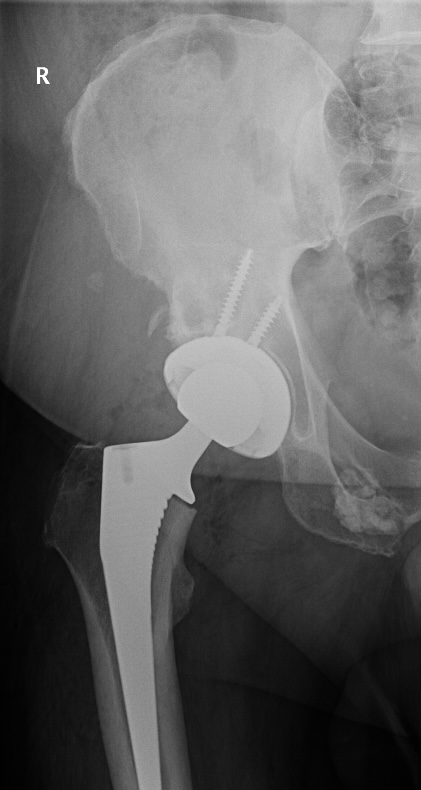

It’s moving slow but improving a little bit at a time with small and better movements with all movement with the hip. What i am impressed with is the technology and how this is insert to the Acetabulum ( hip socket ) – Femoral Head has 2 – 2 – inch screws attached to it – Femoral neck which runs through to the Femur were the 6 inch rod is drilled in to your thighbone, with recovery around another six weeks and improving each week Im looking forward to be back to normal movement if any thing better that i have been in years.